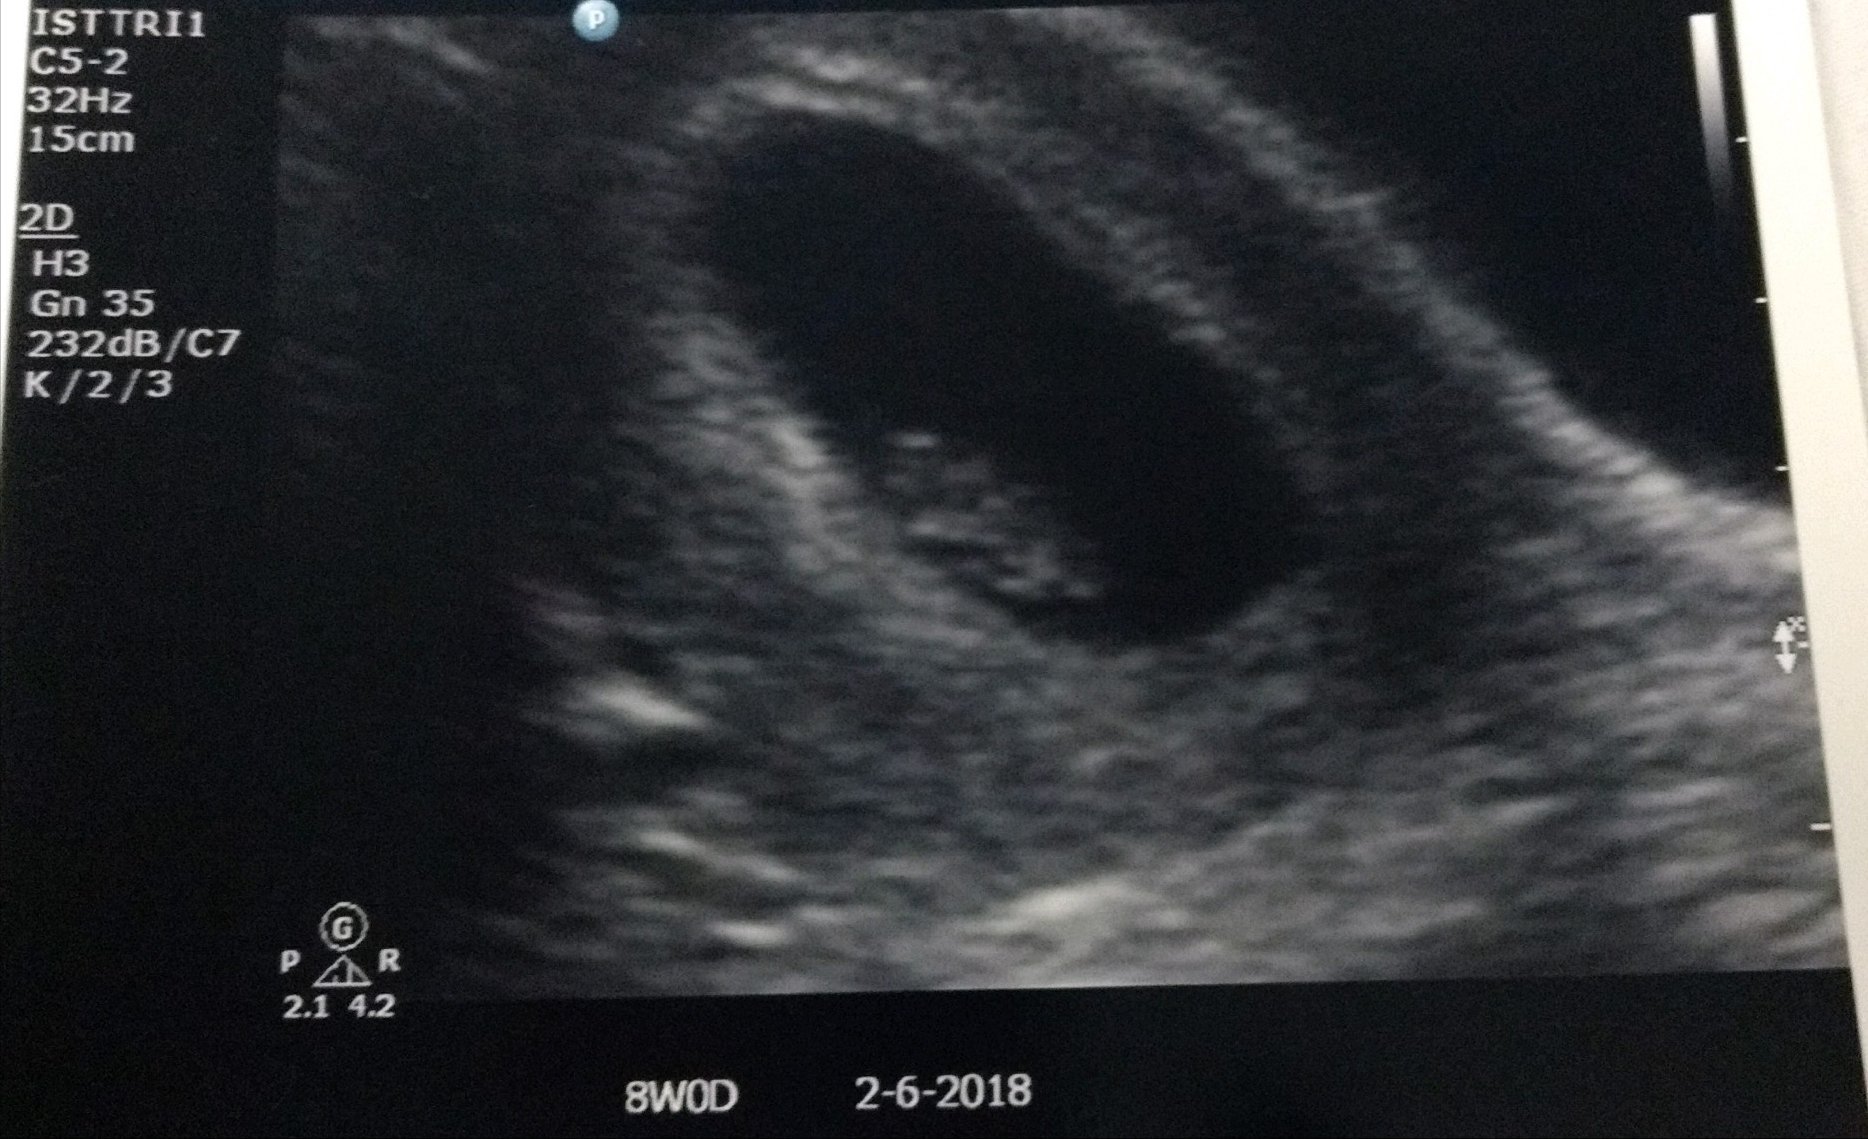

• I'm 9 weeks ( EDD is February 5th). This was my 8 week ultrasound though I was measuring around 8w2d.